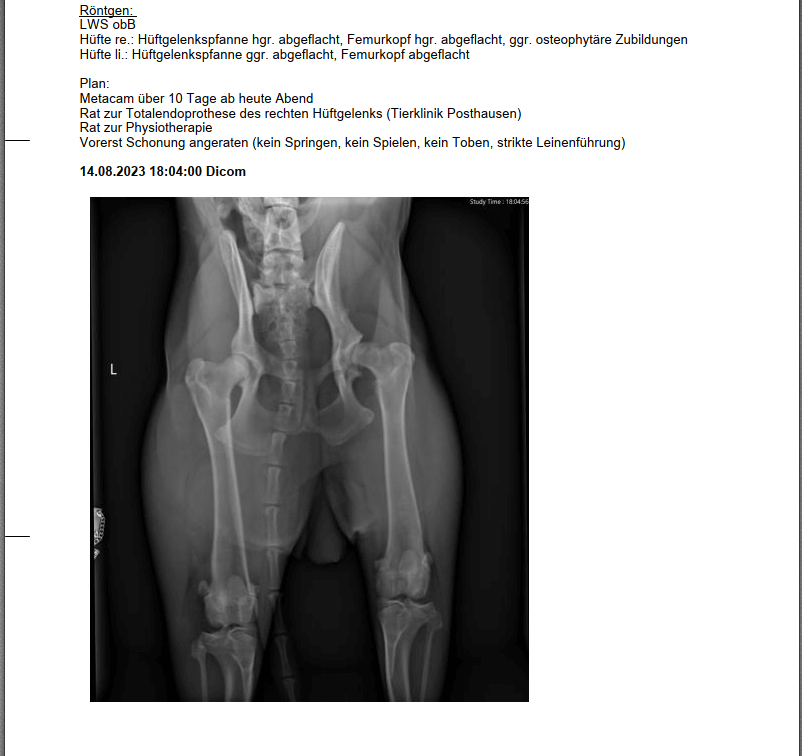

Wir sind also in die Tierklinik nach Lüneburg und haben Madame röntgen lassen - mit der, für uns, niederschmetternden Diagnose rechts hochgradige HD und links geringfügig. Uns wurde von der behandelnden Ärztin geraten uns mit Dr. Schmierer aus Posthausen in Verbindung zu setzten, da uns eine Totalendoprothese angeraten wird, neben Physio. Eine Beckenschwenkostemie würde für uns nicht in Frage kommen.

So das zu den "überschaubaren" Hintergrundinformationen. Ich hänge euch mal das Röntgenbild an, vielleicht sind hier ja ein paar versiertere Menschen, als ich das bin, auf dem Gebiet unterwegs und kann uns vllt. ein wenig dazu sagen. Macht es Sinn, Dr. Tellhelm mit ins Boot zu holen, um die Bilder nochmals zu analysieren oder scheint der Fall glasklar?